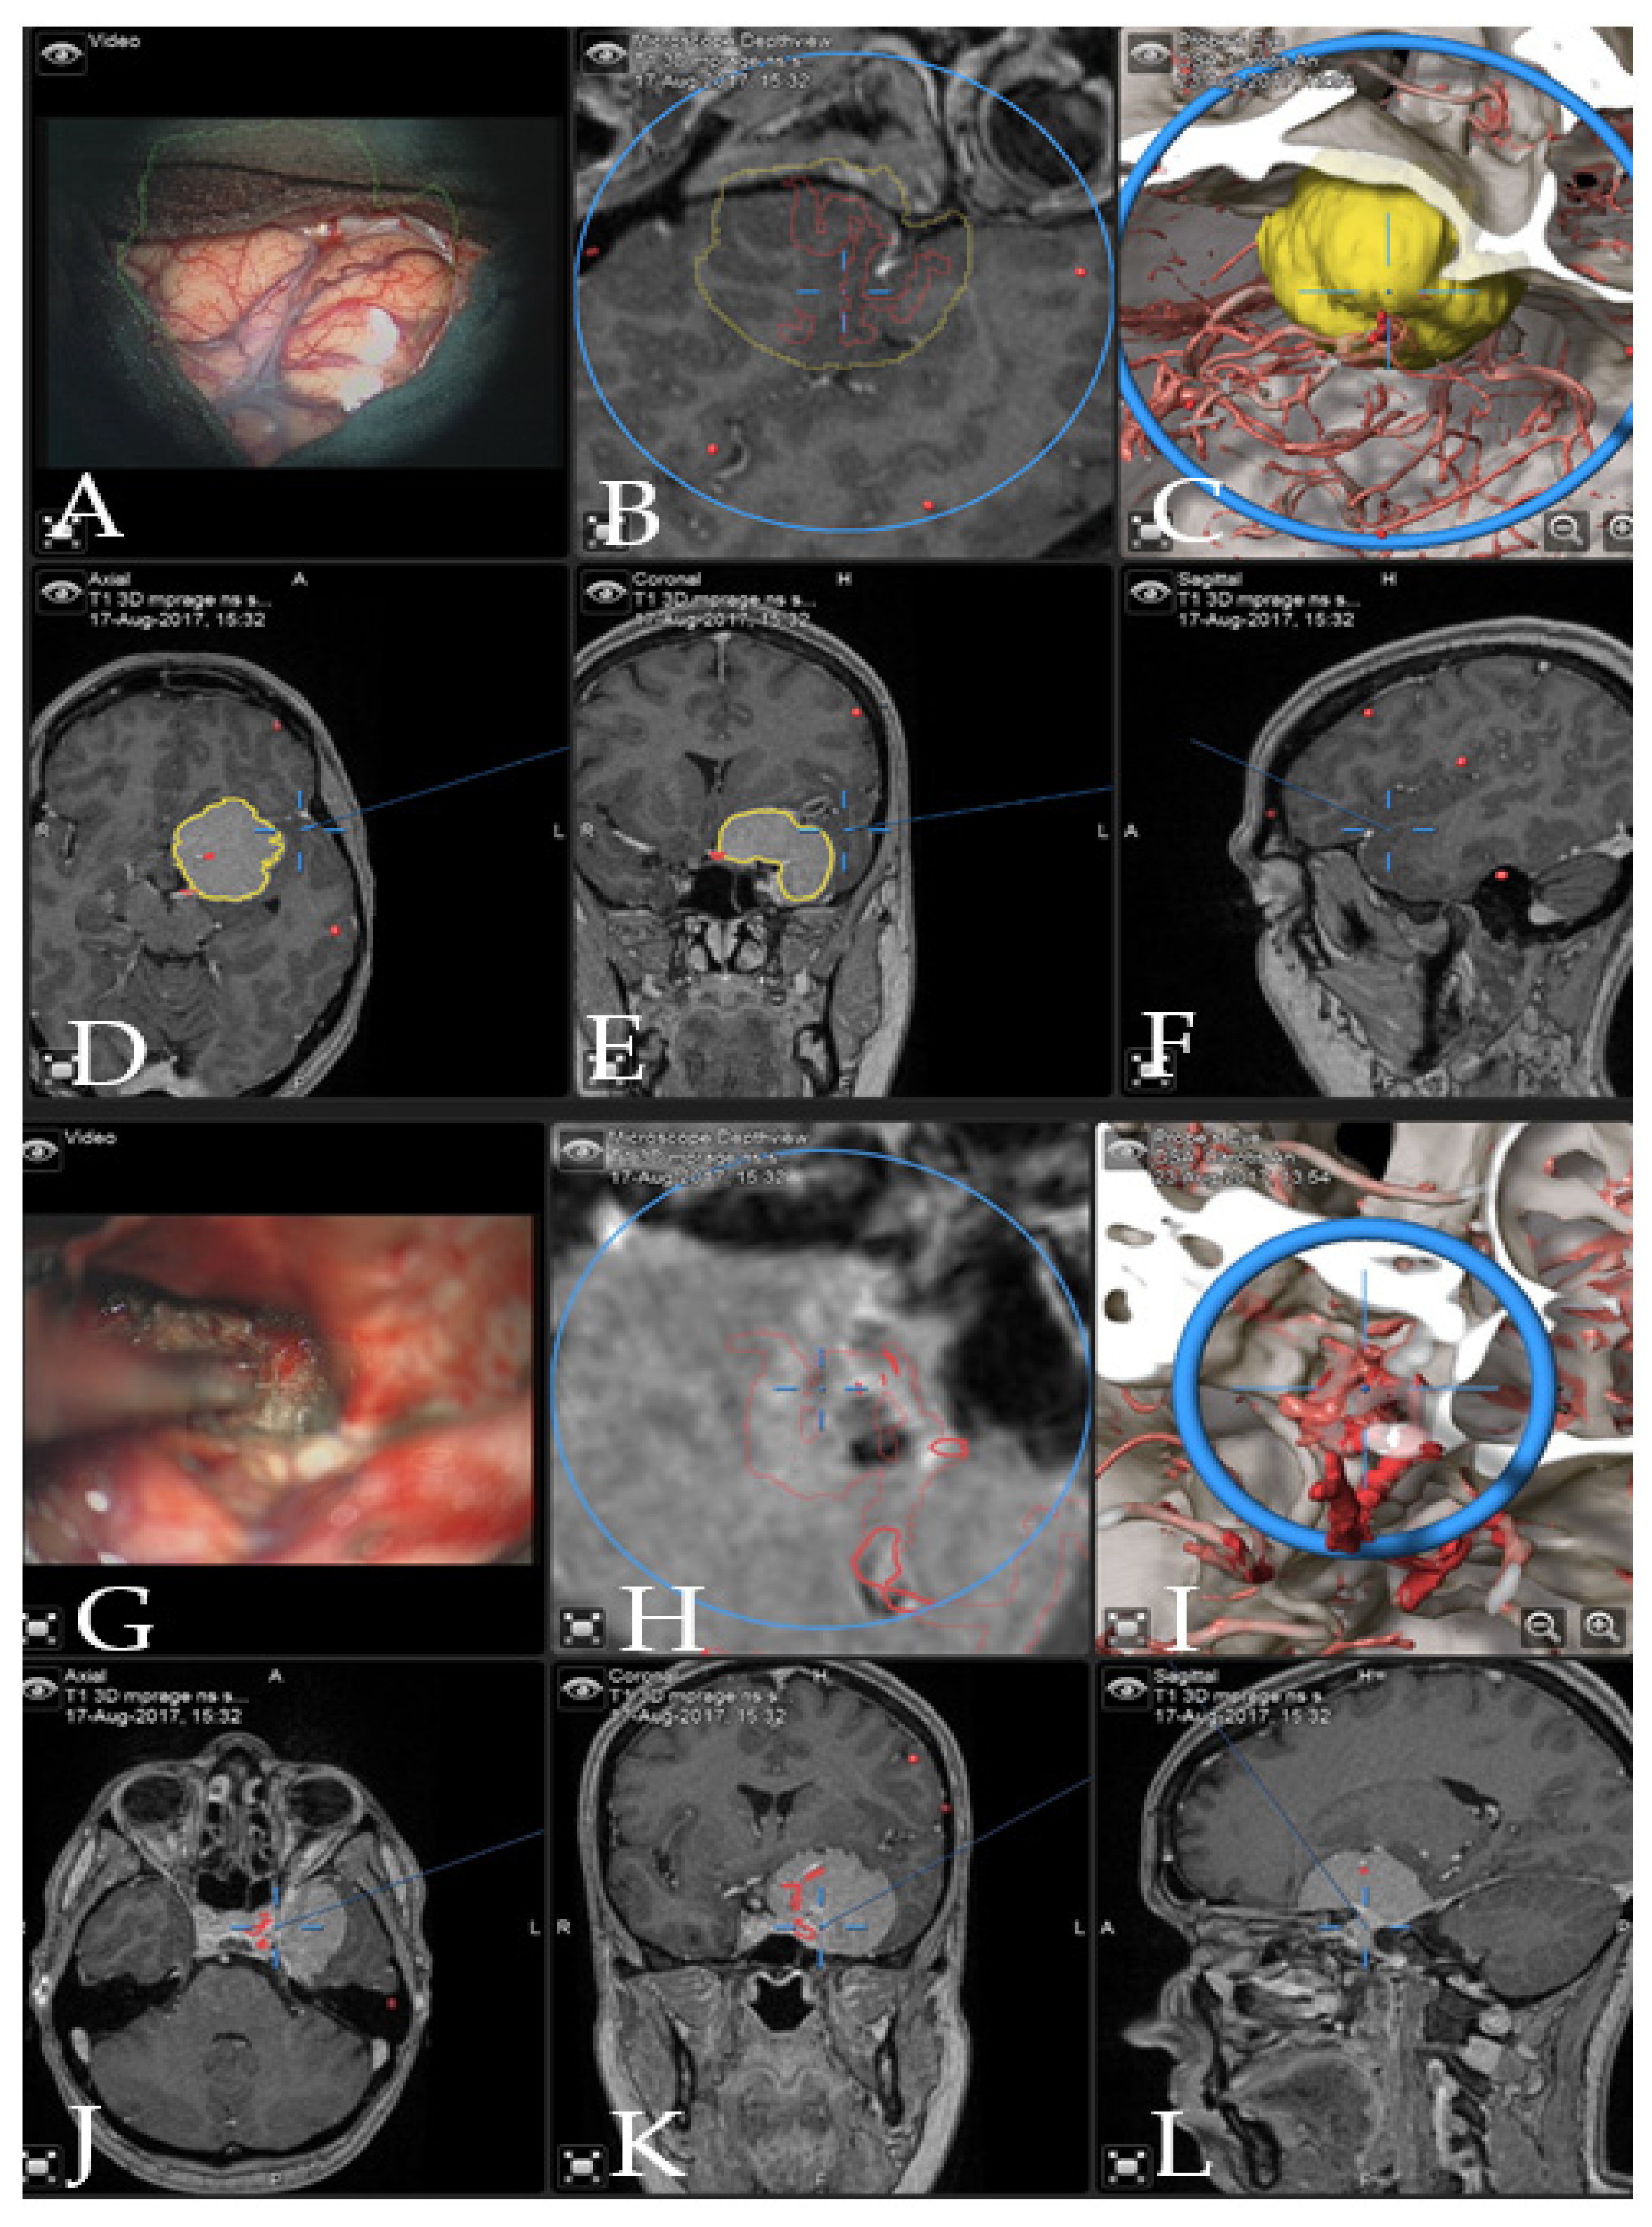

Figure 3. Navigation and AR support during surgery (patient no. 28). (A) Microscope video with head-up display and 3-dimensional (3D) visualization of the segmented objects (tumor in yellow, carotid and anterior cerebral arteries in blue, optic chiasm in yellow). (B,C) Probe’s eye view in 2D and 3D mode. Navigation display in (D) axial, (E) coronal and (F) sagittal view with the segmented objects (focus on the tumor following debulking). (G) AR display on video screen with the 3D outline of tumor, carotid arteries, optic nerves and chiasm. (H) Corresponding probe’s eye view. (I) Target view (tumor and further objects outside of the focus plane are visualized) and (J) video plane in relation to the 3D objects.

Case 1: Patient no. 28 was a 77-year-old female patient with right clinoidal meningioma who experienced visual field deficits and visual deterioration. A complete resection of the tumor was performed via right fronto-temporal craniotomy. AR support facilitated the course of the resection with prompt localization of the segmented carotid and cerebral arteries, as well as the optic chiasm, providing surgical precision throughout the procedure. Figure 3 demonstrates navigation and AR support at the beginning of the tumor resection and Figure 4 shows the microscopic view following the gross total resection of the tumor. The patient recovered fully and was neurologically intact. Operative video has been added to Supplementary Materials: Video Pt 28.

Case 2: A 38-year-old female patient with giant medial sphenoid wing meningioma on the left side presented with vertigo (patient number 9). GTR was performed using iCT-based navigation registration and microscope-based AR. Figure 5 demonstrates the intraoperative view throughout the resection and Figure 6 shows preoperative and postoperative MRI imaging. The patient recovered fully and had no neurological deficits. Operative video has been added to the Supplemental Materials: Patient number 9.